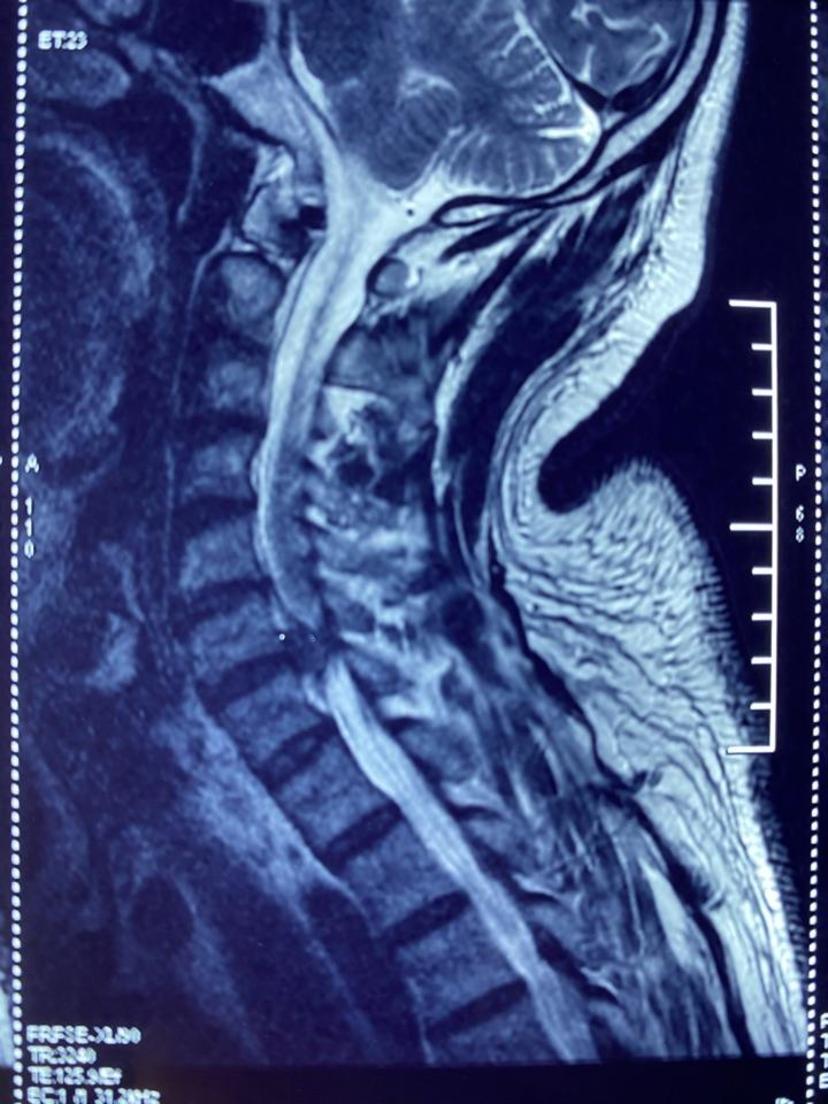

患者颈部疼痛,上肢酸痛麻木,行走不稳,经过颈椎磁共振+颈椎CT检查,颈6-7椎间盘脱出导致椎管狭窄,颈5-6层面后纵韧带骨化及大量骨赘,均采用前路单间隙减压微创术式,避免了椎体切除,术中出血少、手术时间短、术后三天出院,不适症状完全消失!磁共振显示颈6-7椎间盘脱出占满整个椎管空间,脊髓完全受压